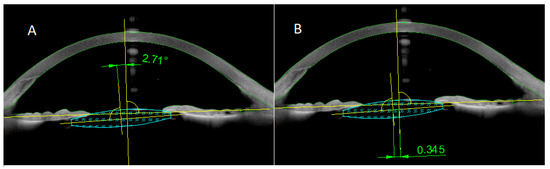

Background: To compare tilt and decentration results of two scleral fixation intraocular lens (IOL) methods of four-point scleral fixation (Akreos AO60) and the Yamane technique (AcrySof MA60AC). Methods: Two groups were compared in terms of IOL decentration and tilt at day [...] Read more.

Background: To compare tilt and decentration results of two scleral fixation intraocular lens (IOL) methods of four-point scleral fixation (Akreos AO60) and the Yamane technique (AcrySof MA60AC). Methods: Two groups were compared in terms of IOL decentration and tilt at day 30 and 2 years after surgery. Correlations between IOL tilt and decentration and previous pars plana vitrectomy (PPV), axial length (AL), refractive error (RE), astigmatism, and spherical equivalent (SE) were also analyzed. Results: This study included 50 eyes from 47 patients: four-point fixation in 25 eyes (group 1) and Yamane technique in 25 eyes (group 2). The mean horizontal tilt was 1.66° ± 1.45° in group 1 and 5.06° ± 4.65° in group 2. The horizontal tilt value was significantly higher (p < 0.05) in group 2. The mean vertical tilt for group 1 and group 2 at two year’s observation was 1.74° ± 2.16° and 3.09° ± 2.79° respectively (p = 0.02). The mean horizontal IOL decentration was 0.35 ± 0.32 mm in group 1 and 0.34 ± 0.26 mm in group 2 (p > 0.05). The mean vertical IOL decentration in group 1 was 0.34 ± 0.33 mm and in group 2 it was 0.27 ± 0.20 mm respectively (p = 0.45). No statistically significant changes in tilt and decentration time were demonstrated in both groups (p > 0.05). There was no statistically significant correlation between IOL tilt and decentration and previous PPV in both groups. Conclusions: Both techniques provide good centration and stability IOL in aphakic eyes in the absence of capsular support. Full article